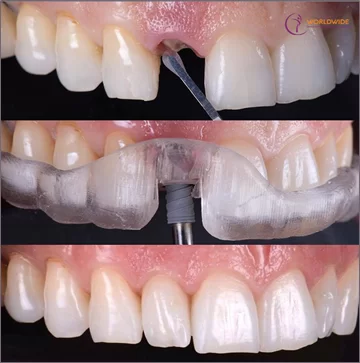

2. Phục hình Implant

Sau khoảng 4-6 tháng đặt Implant, bác sĩ sẽ đặt 1 trụ lành thương (Healing cap) trên Implant. Cần từ 1 đến 2 tuần cho mô nướu phát triển quanh trụ lành thương để đảm bảo tính thẩm mỹ cao cho phục hình trên Implant giống như răng thật. Sau đó, bác sĩ tiến hành đặt khớp nối (Abutment) trên Implant và lấy dấu bằng các vật liệu & dụng cụ chuyên biệt, đồng thời chọn màu răng sứ cho phù hợp với màu răng tự nhiên của bạn.

Tại Worldwide, cùng với kế hoạch phục hình đã thiết lập từ trước, toàn bộ các dữ liệu trên được chuyển đến labo răng giả của Kubet. Răng sứ trên Implant sẽ được thực hiện tại Lab in-house theo công nghệ CAD/CAM (với toàn bộ hệ thống máy móc, thiết bị, vật liệu của Đức) trong vòng 24 giờ (từ 1 đến 3 răng) và từ 2 đến 3 ngày cho các trường hợp nhiều Implant và phức tạp hơn. Sau khi labo đã hoàn tất răng sứ, bác sĩ sẽ thử răng cho bạn và sau đó gắn chặt răng sứ trên Implant bằng cement hoặc ốc vặn, hoàn tất quy trình cấy ghép Implant.